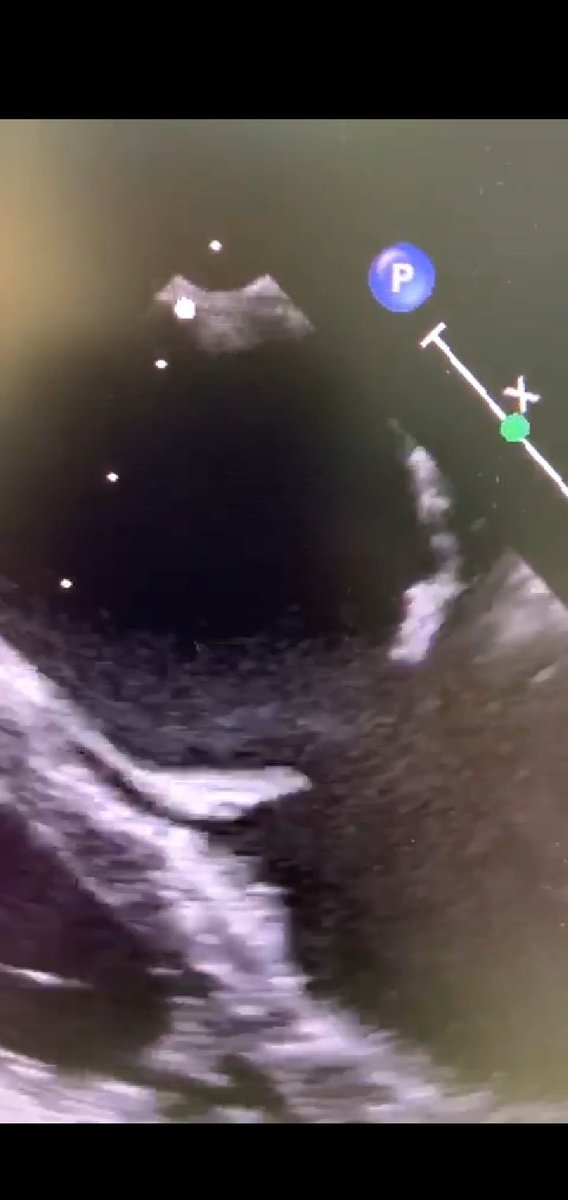

يسألنى الكثير عن ضيق الصمام الميترالي الناتج عن الحمه الروماتيزميه.. هو ضيق ناتج عن التهاب الصمام الميترالي نتيجة أصابه هذه الصمامات ببكتيريا معينه خلال الطفوله.ينتج عن الضيق كتمه فى النفس.العلاج أما جراحى او عن طريق القسطره اذا كان مناسب. هذه صور من مركزنا لعلاج مريضه بالقسطره.

ان برنامج علاج أمراض الصمام الميترالي عن طريق القسطره بمركز الملك فيصل لأمراض القلب بالحرس الوطني بجده يعتبر احد اهم المراكز فى تقديم هذا النوع من العلاج.. حيث يتم علاج ارتجاع الصمام او ضيق الصمام بالقسطره اذا كان مناسب.. هذه حاله توسيع الضيق باستخدام البالون عملنها بالامس.